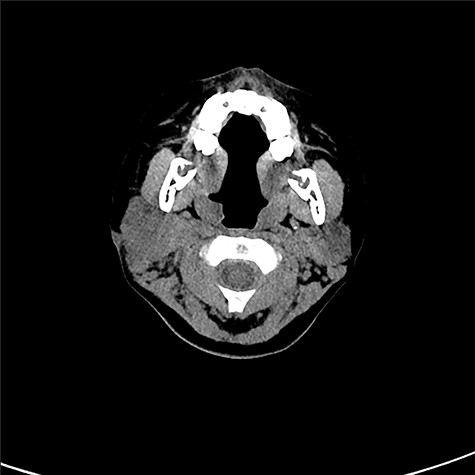

An 8-year-old Japanese girl was introduced to our department from an ear-nose-throat doctor, with a diagnosis of infected epidermal cyst. She had a subcutaneous induration with a diameter of 5 × 12 mm, below the right mandibular angle (Fig. 1). Recurrent inflammation had been persisting for a year. Pediatrist had followed her with a diagnosis of recurrent parotitis. Previously, CT (Fig. 2) and MRI images had been taken and the radiologist found small calcifications in her right parotid gland but no sign of parotitis, cysts or fistula. No other abnormality, including extra auricular canal, was detected. No particular family history was recorded.

CT scan taken prior to the first visit. There can be seen subcutaneous induration, but no cysts nor fistula was obvious.